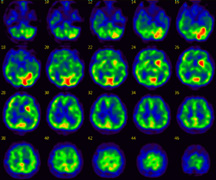

spectの画像

![spect 撮って診る認知症genki55.net|SPECT検査[認知症の進行状況がわかる]](http://genki55.net/img/spect09.gif)